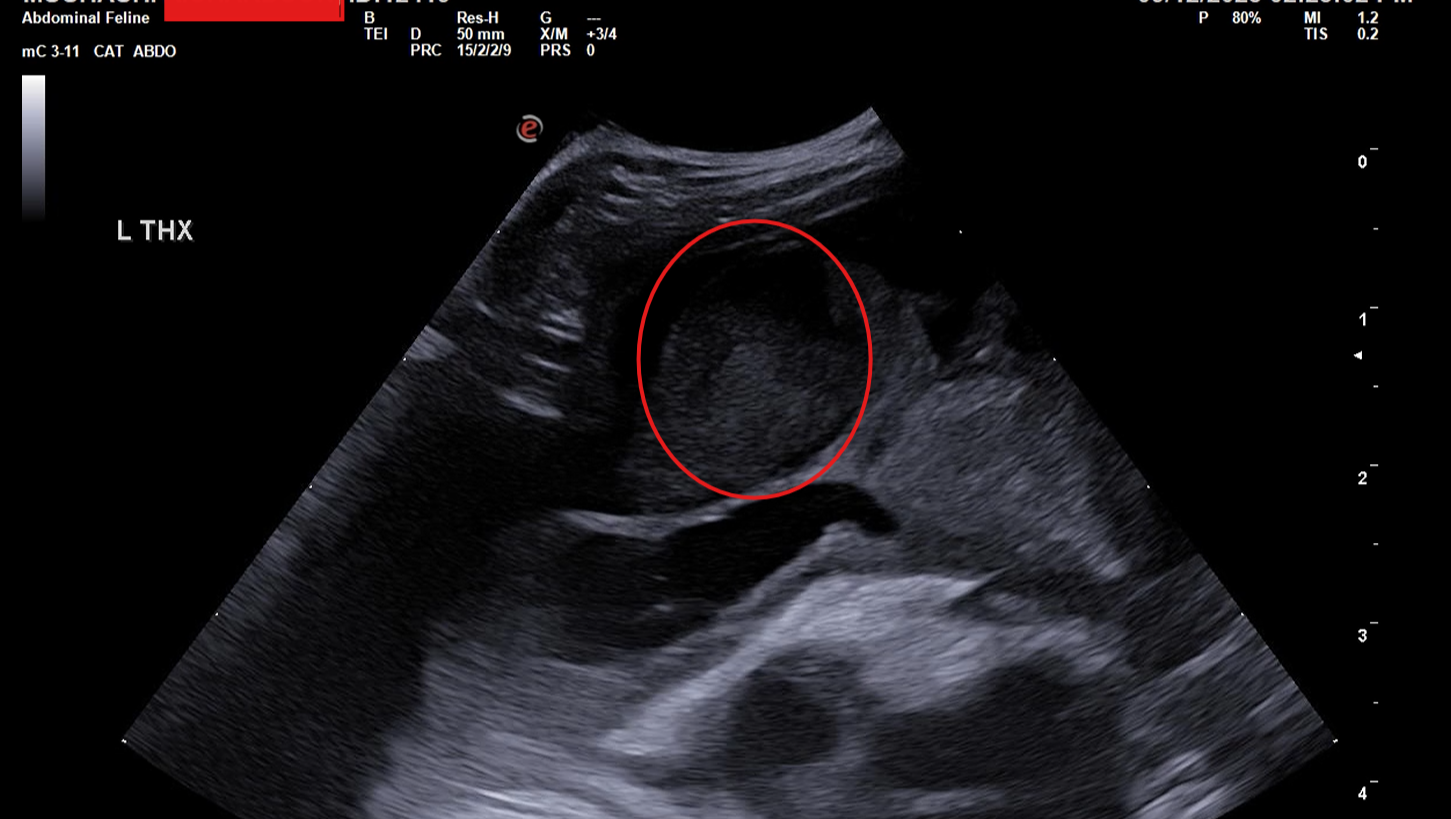

Mushashi suddenly became lethargic, stopped eating, lost weight, and struggled to breathe. He was rushed to the emergency vet, where tests revealed a massive buildup of fluid in his chest cavity (pleural effusion) that was preventing his lungs from fully expanding. The prognosis was grave.

After an emergency procedure to drain the fluid, Mushashi showed incredible resilience — but he is still in critical condition. His medical team now has a high suspicion for Feline Infectious Peritonitis (FIP), a rare and often fatal viral disease.